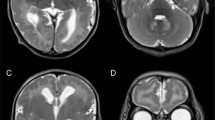

Patient II-2 (Figure 1a), the younger sister of II-1, was born at 39 weeks of gestation without asphyxia 2 years after the death of her older sister. Her body weight was 2500 g (−1.7 s.d.), height 48.2 cm (−0.5 s.d.) and head circumference 32.0 cm (−1.0 s.d.). She was noted to have contractures in all extremities at birth. She was severely hypotonic, and showed poor eye contact and difficulty in feeding. Laboratory analyses revealed normal complete blood counts, liver and kidney function tests, serum electrolytes and creatine kinase levels. Transcranial ultrasonography showed slight atrophy of the cerebellum and brainstem. Brain magnetic resonance imaging revealed abnormal intensity in the subaqueductal area of the midbrain (Figures 2a and b), although the corpus callosum, internal capsule and basal nuclei were spared.

Brain magnetic resonance imaging of patient II-2. A T2-weighted brain magnetic resonance imaging at 1 year of age showed symmetrical high-intensity lesions of the midbrain (a) and slight atrophy of the cerebellum (b). At 7 years of age, the symmetrical high-intensity lesions of the midbrain were unchanged (c), while the diffused cerebellar atrophy was progressive (d).

Levels of lactate and pyruvate in the blood were normal (1.23 and 0.07 mM, respectively; lactate/pyruvate ratio, 17.6), as were cerebrospinal fluid levels (1.76 and 0.04 mM, respectively; lactate/pyruvate ratio, 44.1). The serum beta-hydroxybutyrate/acetoacetate ratio was 3.9. Other laboratory examinations including blood gases, blood sugar, ammonia, aspartate aminotransferase, alanine aminotransferase, blood urea nitrogen, creatinine, amino acids and urine organic acid analyses were all normal. Electroencephalography showed no abnormalities. The left tibial nerve showed decreased conduction velocity (27.7 m s−1). Electrocardiography revealed sinus bradycardia. Despite extensive treatment including an adrenergic agent, she continued to exhibit frequent bradycardia. Repeated brain magnetic resonance imaging demonstrated a progressive cerebral and cerebellar atrophy (Figures 2c and d). Magnetic resonance spectroscopy showed an intense lactate peak of 1.35 p.p.m. and reduced N-acetyl-aspartate levels (Figure 3).

Leigh syndrome is a progressive neurological disease defined by specific neuropathological features associated with lesions in the brainstem and basal ganglia. It may reflect a deficiency of any of the mitochondrial respiratory chain complexes.15, 16 Our patient developed progressive encephalopathy with deteriorating respiratory and psychomotor dysfunction. Magnetic resonance imaging revealed an abnormal intensity in the subaqueductal area of the midbrain with optic and cerebellar atrophy. Although cerebrospinal fluid lactate and pyruvate levels were not increased, an intense lactate peak in the deep white matter was shown in magnetic resonance spectroscopy. Moreover, activities of the oxidative phosphorylation complexes were decreased in skin fibroblasts. Although complexes III and IV activities were not low enough to meet the minor diagnostic criteria for respiratory chain disorders (30–40% activity in a cell line17), these decreased levels might be an evidence of mitochondorial dysfunction caused by GFM2 mutations. Additionally, high lactate/pyruvate and beta-hydroxybutyrate/acetoacetate ratios in the cerebrospinal fluid and serum, respectively, are characteristic of the lesion tissue specificity commonly observed in this syndrome.